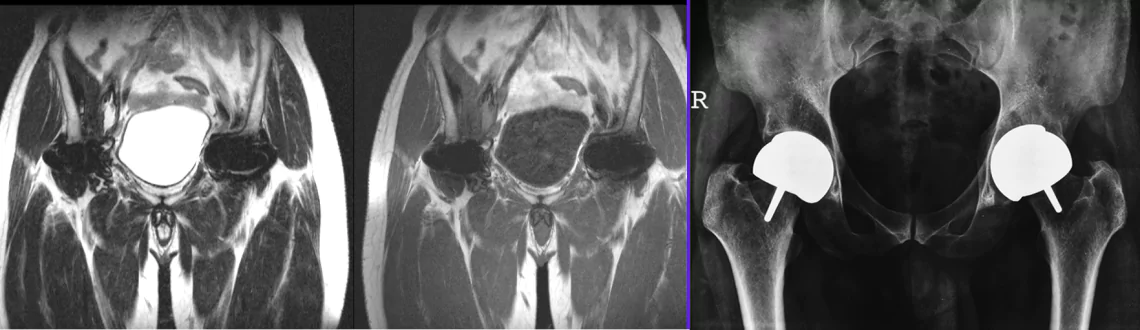

At Picture This, we’re proud to offer Mumbai’s most advanced MARS (Metal Artifact Reduction Sequence) MRI, using the powerful Philips 3.0T Ingenia CX system. MARS MRI is specifically designed to produce crisp, diagnostic-quality images in areas with metal implants-overcoming the limitations of conventional MRI.

MARS (Metal Artifact Reduction Sequence) MRI uses specialized pulse sequences and software algorithms to significantly reduce distortion, streaking, and signal voids caused by metal prostheses, orthopaedic hardware, or dental implants. This enables clear visualization of surrounding soft tissues, joints, and organs for accurate diagnosis and planning.

1. Post‑operative Orthopaedic Evaluation - hips, knees, spine, shoulder implants

2. Implant Surveillance - evaluation around joint replacements, plates, screws

3. Soft Tissue Assessment - bursae, tendons, muscles near metal implants